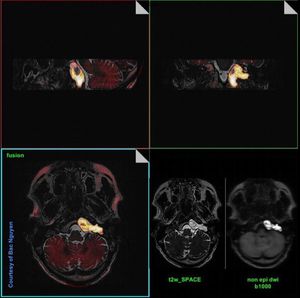

DWI is a useful technique for the evaluation of cholesteatomas. It can be used to detect them when the physical examination is difficult and CT findings are equivocal. Moreover, it is especially useful in the evaluation of recurrent cholesteatoma. Fig. Image fusion --> High resolution T2-w SPACE (modified 3D TSE) sequence, which provides us anatomical information, with a HASTE (single-shot TSE) DWI b1000, which provides us functional information. Non-EPI DWI assists in detection and evaluation of the lesion. Image dataset acquired at Siemens Aera 1.5 Tesla, courtesy of Bac Nguyen.